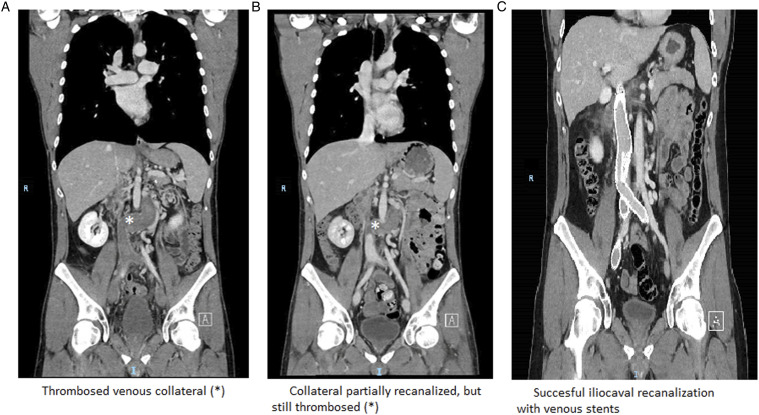

Venous stenting could alleviate exercise intolerance associated with chronic inferior vena cava (IVC) obstruction. We describe a 36-year-old male patient with an unknown IVC-obstruction. The obstruction was discovered after a bi-iliac deep vein thrombosis (DVT). The thrombus was resolved using thrombolysis. In the chronic phase, the patient developed exercise intolerance without any leg-specific symptoms or signs. Venous stenting was performed to open the IVC-obstruction, 1 year after the acute DVT. His physical condition improved, but cardiac magnetic resonance imaging at rest did not reveal hemodynamical changes after stenting. The Short Form Health Survey (SF-36) physical and mental component summaries were increased from 40.3 to 46.1 and 42.2 to 53.7, respectively. In patients with iliocaval obstruction, improved venous flow without changes in resting hemodynamics can enhance exercise intolerance and quality of life, even in the absence of leg symptoms. Diagnostic tools performed only at rest may miss abnormalities.

Abstract Image